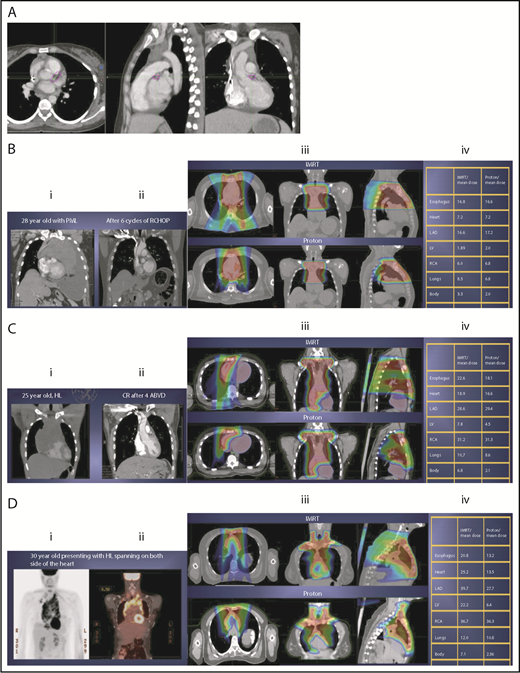

The take-off of the left main stem coronary artery is used to define whether the target is above or below the heart (Figure 2A). In this example (Figure 2B), the exposure of the heart is quite comparable, regardless of which technique is used. Differences in DVHs, as well as the mean dose to other structures, are similar to the proton and IMRT plans.

Three scenarios of the relation between mediastinal disease and the heart. (A) Showing how to use the takeoff of the left main stem coronary artery (outlined in pink) to determine the upper and lower mediastinal locations. (B) Scenario 1: coronal CT images of a 28-year-old man with primary mediastinal lymphoma before (i) and after (ii) 6 cycles of rituximab, cyclophosphamide, doxorubicin, vincristine, prednisone (RCHOP) chemotherapy presenting for consolidation with radiation. (Biii) Axial, coronal, and sagittal views of an IMRT plan (upper panels) and a proton plan (lower panels). (Biv) Corresponding mean doses to critical structures using IMRT vs protons. (C) Scenario 2: coronal CT images of a 25-year-old man with Hodgkin lymphoma before (i) and after (ii) 4 cycles of doxorubicin, bleomycin, vinblastine, and dacarbazine (ABVD) chemotherapy presenting for consolidation with radiation. (Ciii) Axial, coronal, and sagittal views of an IMRT plan (upper panels) and a proton plan (lower panels). (Civ) Corresponding mean doses to critical structures using IMRT vs protons. (D) Scenario 3: coronal CT images of a 30-year-old man with recurrent Hodgkin lymphoma as shown in the coronal images of a PET/CT scan (i-ii) presenting for definitive radiation. (Diii) Axial, coronal, and sagittal views of an IMRT plan (upper panels) and a proton plan (lower panels). (Div) Corresponding mean doses to critical structures using IMRT vs protons.

Scenario 2: target spans the right side of the heart

For the targets on the right side of the heart, IMRT often provide comparable doses to the heart and other structures as proton therapy. Notably, however, even when proton plans give a dosimetric advantage over IMRT plans, the magnitude of advantage could vary between cases, and it needs to be judged individually. For example, for the patient shown in Figure 2C, the mean doses to critical structures from proton therapy are sufficiently lower than those from IMRT to suggest that proton therapy may be preferred because of the large volume spanning the right side of the heart. This example illustrates the need for careful consideration of individual cases before deciding on treatment.

Scenario 3: target is on both sides of the heart

Disease that spans significantly in front of the heart anteriorly, posteriorly, or to the left side poses a particular challenge for IMRT; therefore, proton therapy may be the superior plan. Notably, toxicity to the heart and lungs is not eliminated by using proton therapy; rather, the dose to the heart may be lower than IMRT. Thus, for cases like in Figure 2D, clinicians should carefully weigh the therapeutic benefit against the long-term risks for radiation-induced treatment toxicities before deciding on which technique should be used. Indeed, in this case, proton therapy can significantly avoid the heart and should be sought in an attempt to reduce the dose to the heart substructures.